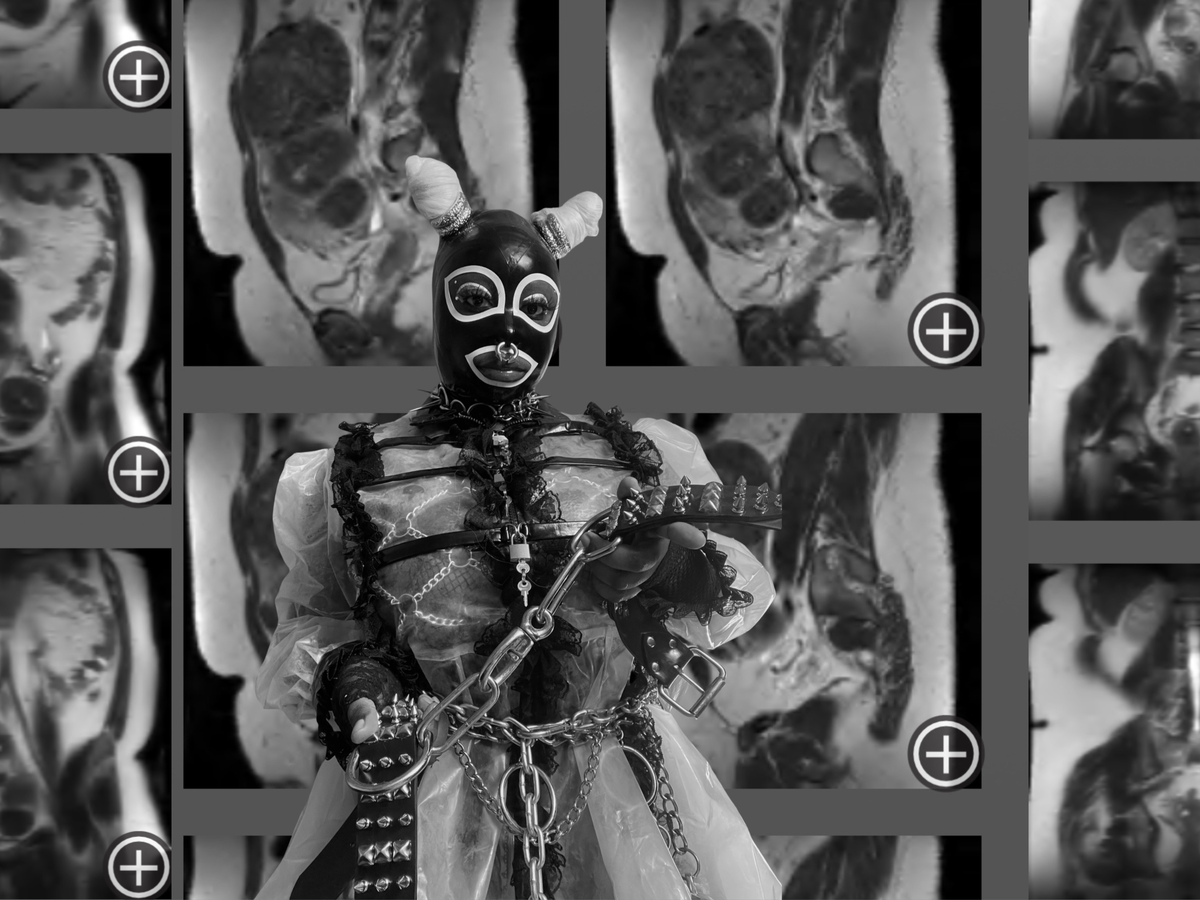

Uterine Fibroids are noncancerous growths of the uterus that are extremely common for Black women. Unfortunately, my pelvic sonogram showed a markedly enlarged uterus with 5 medium-sized fibroids and other smaller fibroids. (doctor informed me there’s 30+.) To give you an example of the sizes of my fibroids, they all vary between as small as a strawberry and as large as a grapefruit or small watermelon.